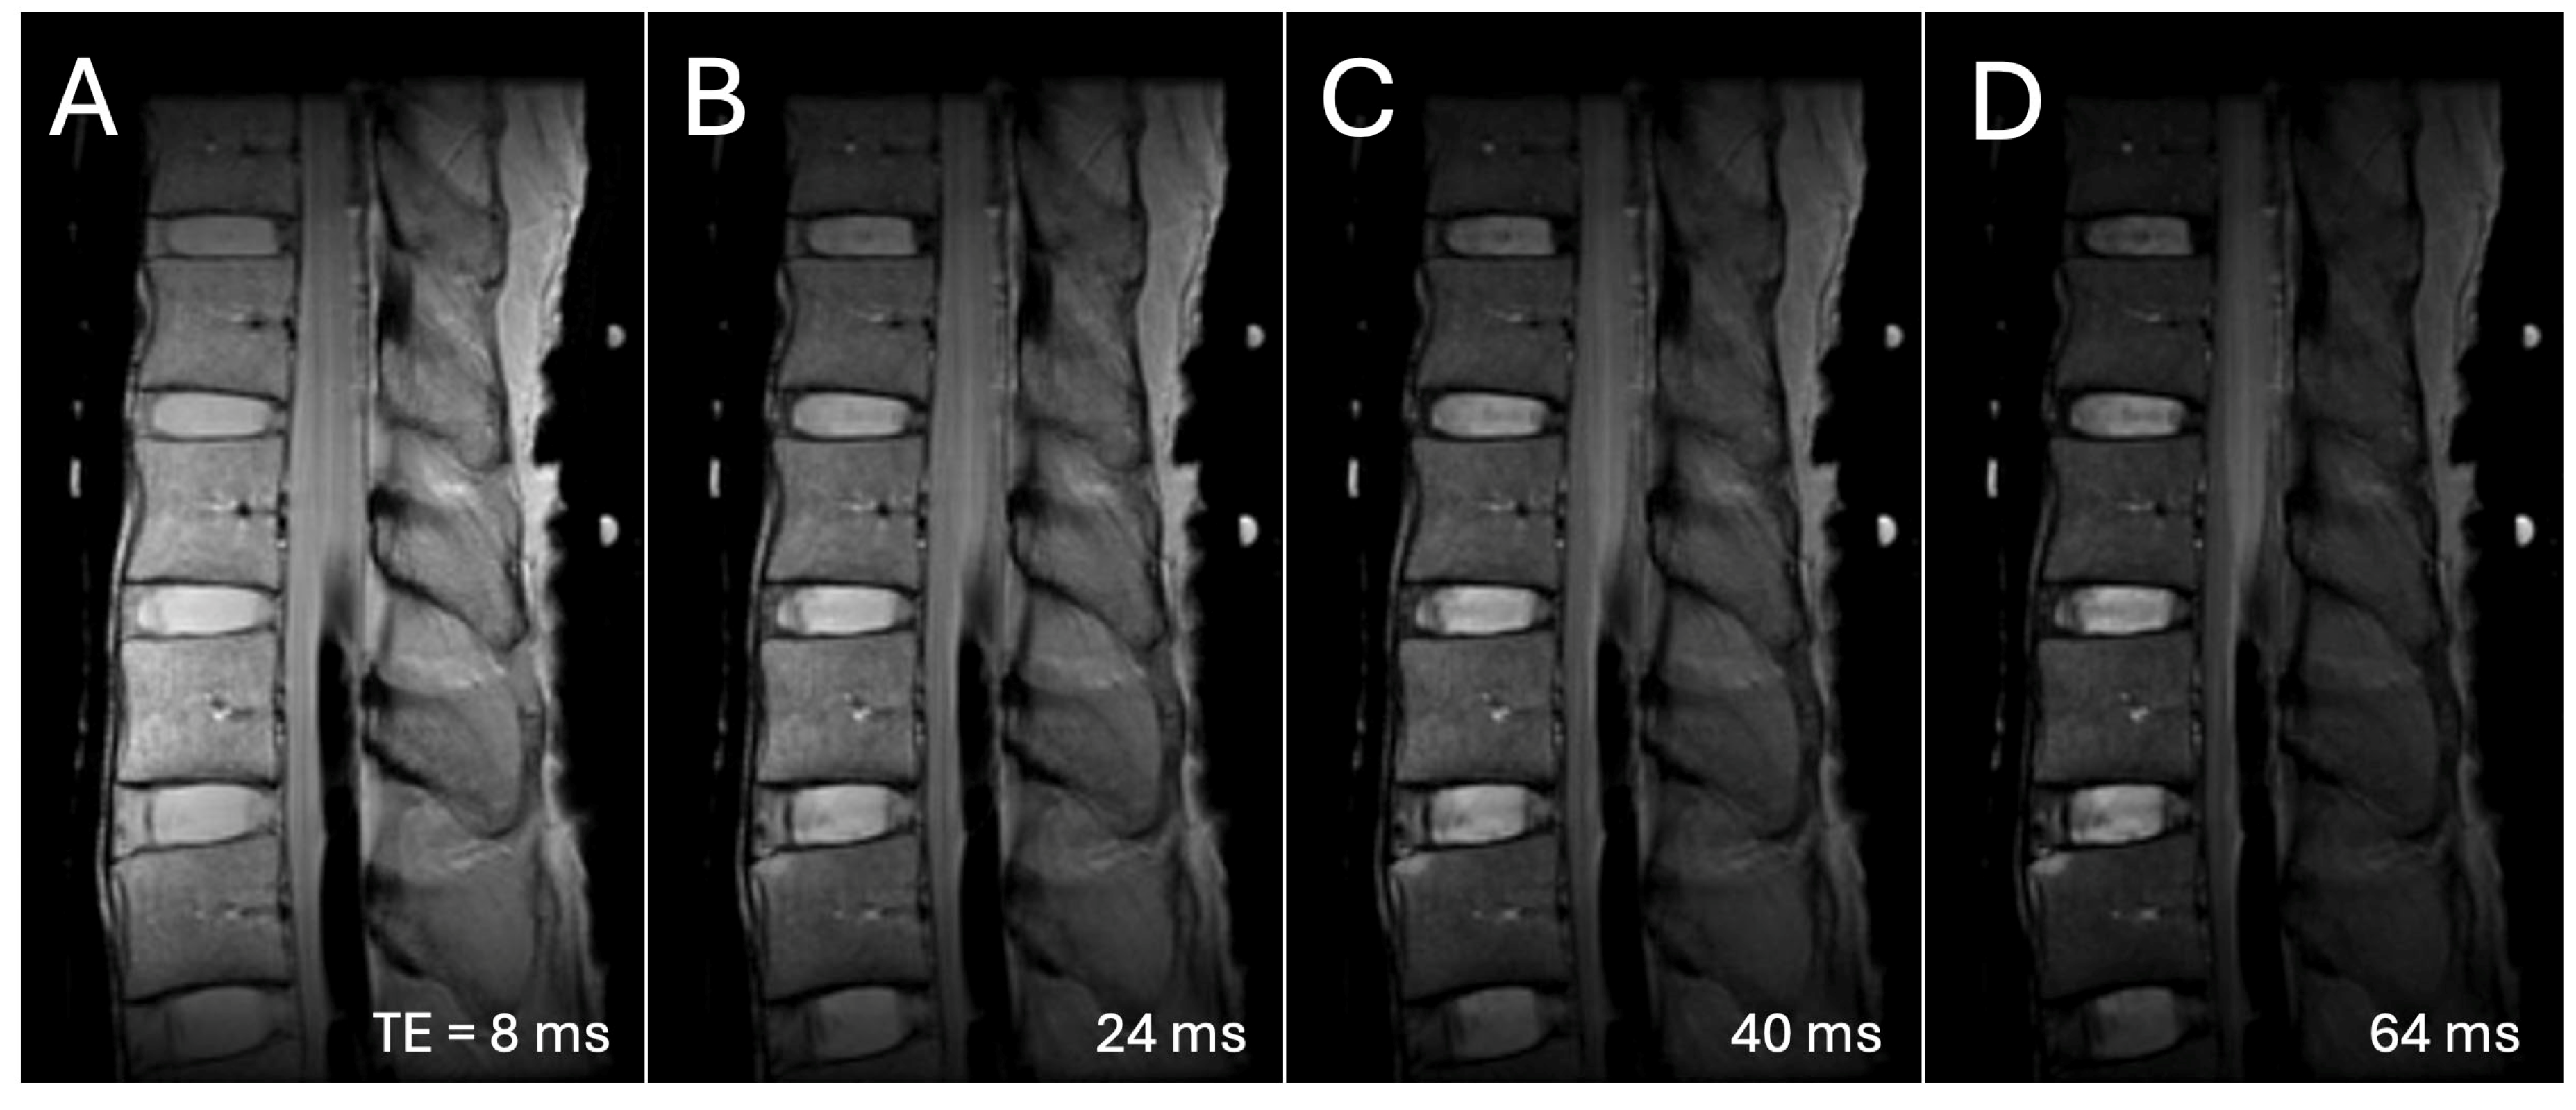

- Takashima, H.; Yoshimoto, M.; Ogon, I.; Takebayashi, T.; Imamura, R.; Akatsuka, Y.; Yamashita, T. T1rho, T2, and T2* relaxation time based on grading of intervertebral disc degeneration. Acta Radiol. 2023, 64, 1116–1121. [Google Scholar] [CrossRef]

- Marinelli, N.L.; Haughton, V.M.; Anderson, P.A. T2 relaxation times correlated with stage of lumbar intervertebral disk degeneration and patient age. AJNR Am. J. Neuroradiol. 2010, 31, 1278–1282. [Google Scholar] [CrossRef]

- Trattnig, S.; Stelzeneder, D.; Goed, S.; Reissegger, M.; Mamisch, T.C.; Paternostro-Sluga, T.; Weber, M.; Szomolanyi, P.; Welsch, G.H. Lumbar intervertebral disc abnormalities: Comparison of quantitative T2 mapping with conventional MR at 3.0 T. Eur. Radiol. 2010, 20, 2715–2722. [Google Scholar] [CrossRef]